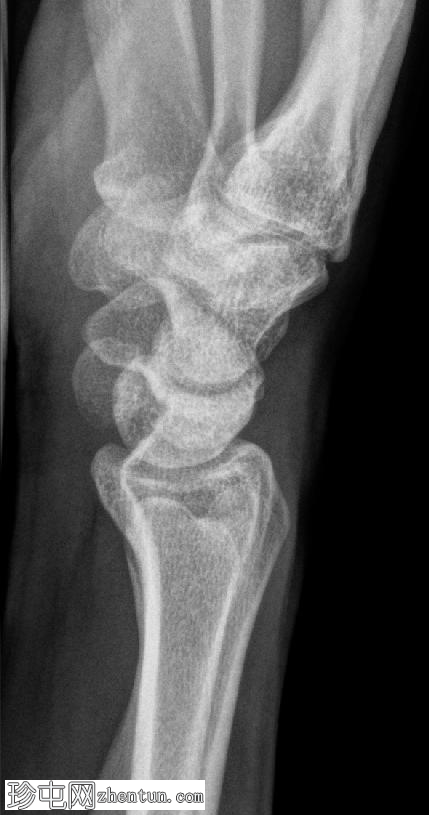

侧位片

可见豌豆骨皮质明显中断,并伴有一小块邻近骨碎片,符合皮质骨折的表现。此外,其上方软组织肿胀,提示急性骨折。

尺骨茎突可见透亮区,符合无移位尺骨茎突骨折的表现。